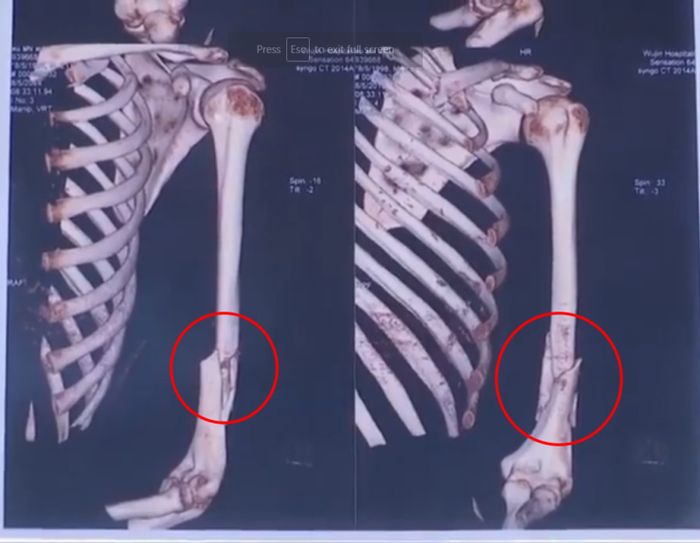

Lihat Hasil X-ray Bikin Ngilu! Begini Ternyata Patah Tulang Humerus Marc Marquez, Pelat dan 12 Baut Titanium Terpasang - GridOto.com

Lihat Hasil X-ray Bikin Ngilu! Begini Ternyata Patah Tulang Humerus Marc Marquez, Pelat dan 12 Baut Titanium Terpasang - GridOto.com

Ngilu Banget, Before-After Kondisi Patah Tulang Marc Marquez

Ngilu Banget, Before-After Kondisi Patah Tulang Marc Marquez